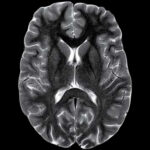

Magnetic Resonance Imaging is a medical imaging technique that uses strong magnetic fields and radio waves to create detailed images of the inside of the body. MRI provides valuable information about the structure and function of organs, tissues, and various parts of the body, making it a powerful tool for diagnosing and monitoring a wide range of medical conditions.

MRI is a versatile imaging technique that can be used to examine various parts of the body, including the brain, spine, joints, abdomen, and pelvis.

It is particularly useful for visualizing soft tissues like organs, muscles, tendons, ligaments, and the central nervous system. Unlike X-rays or CT scans, MRI does not use ionizing radiation, making it a safer option for many patients, including pregnant women and children. MRI is a valuable tool in modern medicine, providing non-invasive and detailed imaging that helps healthcare professionals make accurate diagnoses and develop effective treatment plans for patients.